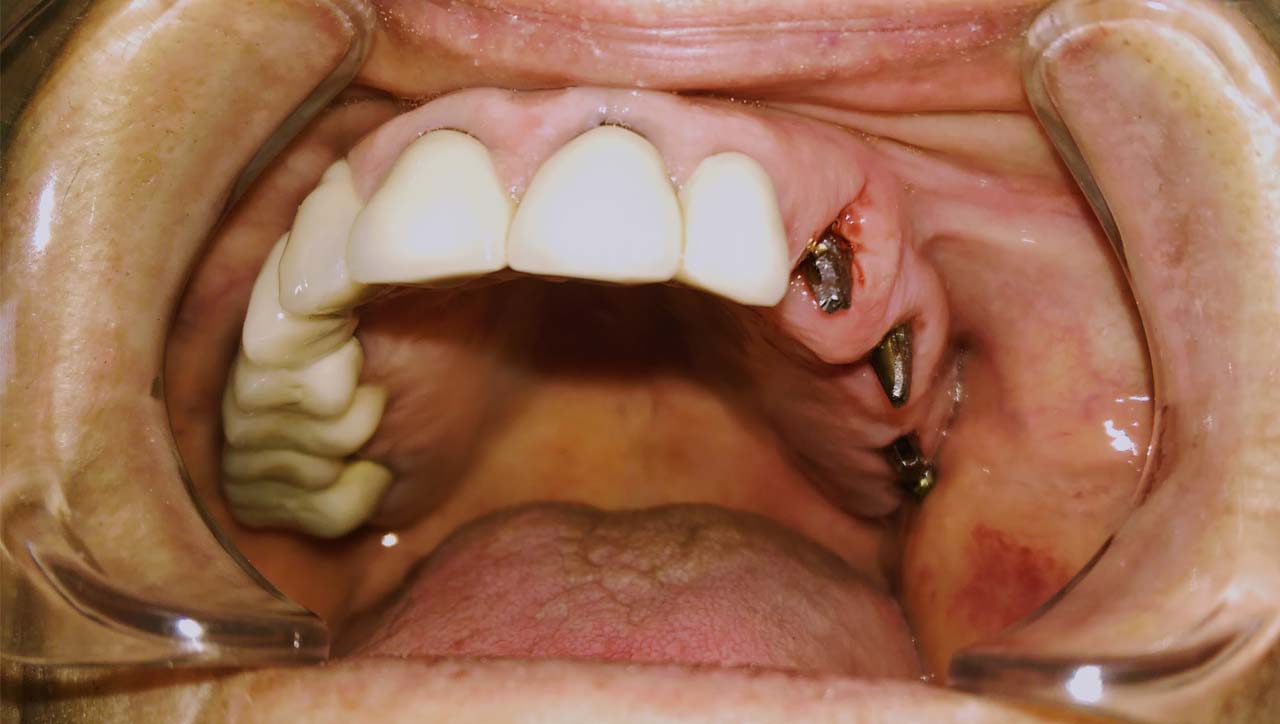

Foghiányos, fertőző gyökerekkel teli szájüreg helyreállítása

Foghiányos, fertőző gyökerekkel teli szájüreg helyreállítása esztétikailag és funkcionálisan 9 nap alatt.

A rossz fogakat és gyökereket eltávolítottuk, és azonnal terhelhető IHDE svájci implantátumokkal pótoltuk.

Az esztétikus koronák cirkóniumból készültek, hogy természetesebb hatást érjünk el